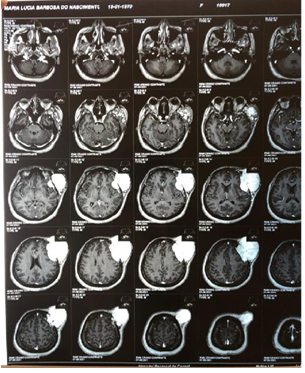

Figure 2A Contrast-enhanced magnetic resonance imaging showing a tumor in the extraaxial region of left frontal involvement.

Figure 2B Contrast-enhanced magnetic resonance image showing a tumor in the extraaxial region of left frontal involvement.

Figure 3A Contrast-enhanced magnetic resonance image showing a tumor in the extraaxial region of left frontal involvement

Figure 3B Contrast-enhanced magnetic resonance imaging showing a tumor in the extraaxial region of left frontal involvement in coronal section.

Figure 5A Contrast-enhanced magnetic resonance image showing a tumor in the extraaxial region of left frontal involvement with axial section.

Figure 5B Contrast-enhanced magnetic resonance imaging showing a tumor in the extraaxial region of left frontal involvement.

Figure 6A Contrast-enhanced magnetic resonance imaging showing a tumor in the extraaxial region of left frontal involvement.

Figure 6B Contrast-enhanced magnetic resonance imaging showing a tumor in the extraaxial region of left frontal involvement.

Patient arrived at the service of the Cacoal Regional Emergency and Emergency Hospital (HEURO) with hospitalization on 07/07/2021, 50 years old, female, black, with a previous history of controlled systemic arterial hypertension and reports a tumor in the left frontal region for about 3 years, visible and with an expansive mass. In view of this, a previous biopsy of oncotic aspiration cytology compatible with a benign follicular nodule (Category II-BETHESDA) was requested, where smears showing moderate cellularity were found at the expense of isolated follicular cells, sometimes aggregated amidst histiocytes, lymphocytes and neutrophils, on an amorphous background with a proteinaceous appearance, in addition to abundant colloid and numerous erythrocytes. The immunohistochemical examination showed the diagnosis of epithelial neoplasia of follicular origin and the anatomopathological analysis in the microscopy part showed the presence of an expansive lesion in the left frontal region suggestive of primary epithelial neoplasia with findings of irregular nuclei with clear areas and lumens filled with amorphous material eosinophilic. The macroscopic analysis showed 3 irregular brownish elastic fragments with dimensions of 0.5 cm x 0.3 cm x 1 cm. After performing magnetic resonance imaging, a left frontal extraaxial lesion with bone destruction was evidenced and the patient was immediately referred to a place in a reference service.

Epithelial neoplasms arise from the so-called follicular cells that have their development associated with the influence of thyroid hormones in the tissues.4 In this case report, the appearance of an expansive and compressive tumor in the extra axial region of the left forehead is observed in a female patient. A 50-year-old patient in category II of the Bethesda classification, widely used to evaluate the aspiration cytological results, found a benign nodular pattern of follicular cells in that atypical area, being indicative of an epithelial neoplasm. Therefore, it reflects on the influence of thyroid hormones that generally affect women eight times more often than men.1 With advancing age, many endocrine systems show a gradual change in production, metabolism, action and plasma concentration of hormones, therefore, it is observed that the serum levels of T3 and T4 are reduced and normal or slightly increased levels of TSH and, therefore, an increase in the prevalence of thyroid disorders among geriatric patients is observed, reaching around 2 .0% to 4.0%, while in the general population the prevalence is 0.5% to 1.0%.5,6 Around the age of 50, women experience hormonal changes with hypoestrogenemia and serum levels of follicle stimulating hormone (FSH) that directly impact the follicular cells contributing to the appearance of epithelial neoplasms.7 After the resonance, another aspect of relevance and concern in the case was evidenced, the fact that there is bone destruction in the region affected by the tumor and the patient is urgently referred to a reference unit (Figure 1A - Figure 6B).